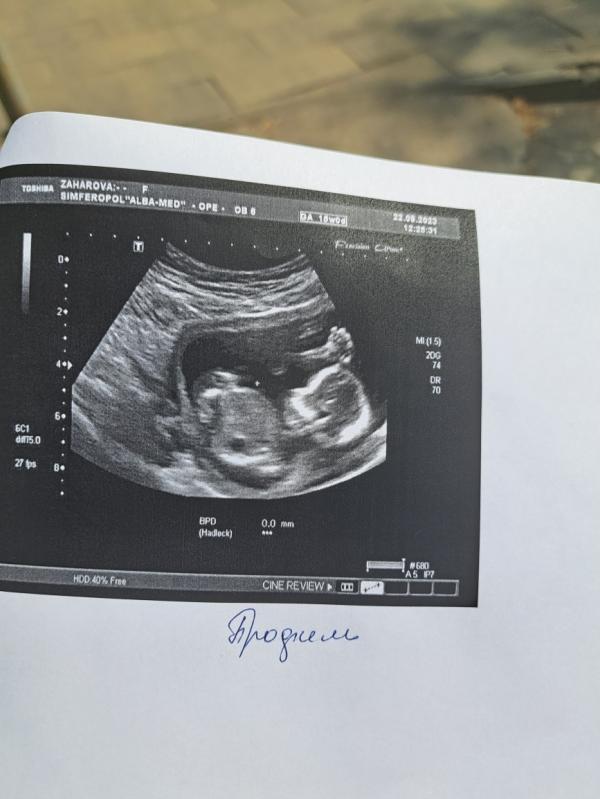

Давно меня не было, много дел навалилось, вот была 22 числа на мониторинге(1 и 2 фото), хотела узнать пол для Гендер Пати, но малыш решил не показывать, между ног пуповину держал и махал ручкой)😁